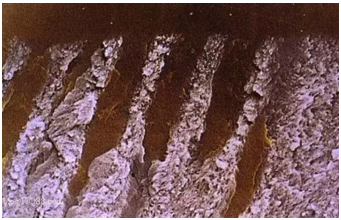

圖示牙本質(zhì)全酸蝕后管間牙本質(zhì)膠原纖維網(wǎng)充分暴露

放大的膠原纖維網(wǎng)(放大倍數(shù)2000)